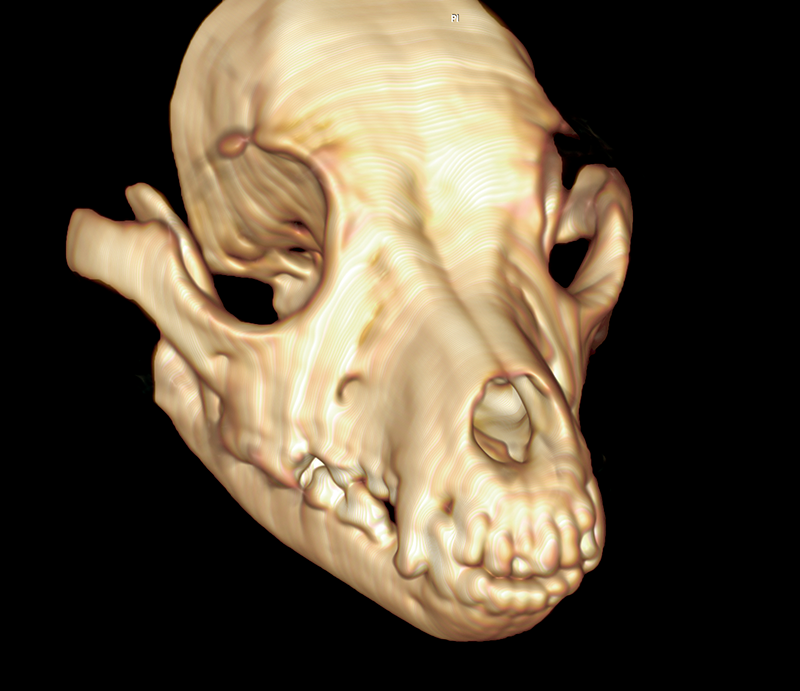

Renderización 3D del mismo animal de la tomografía lateral que nos proporciona una idea del volumen a vaporizar durante la cirugía. La osificación parcial del tumor que muestra la tomografía, hará necesario el trabajo en modo contacto que maximice la densidad de poder del haz láser

La cirugía termina cando se ha eliminado la masa por completo, además de los márgenes de seguridad que hayamos establecido, si nuestra intención es curativa o cuando consigamos disminuir si tamaño a aquel que elimine los sintomas y mejore la calidad de vida del animal si nuestro planteamiento terapeutico es paliativo. Las imágenes muestran una tomografía posoperatoria del mismo punto anatómico una vez eliminado el tumor.